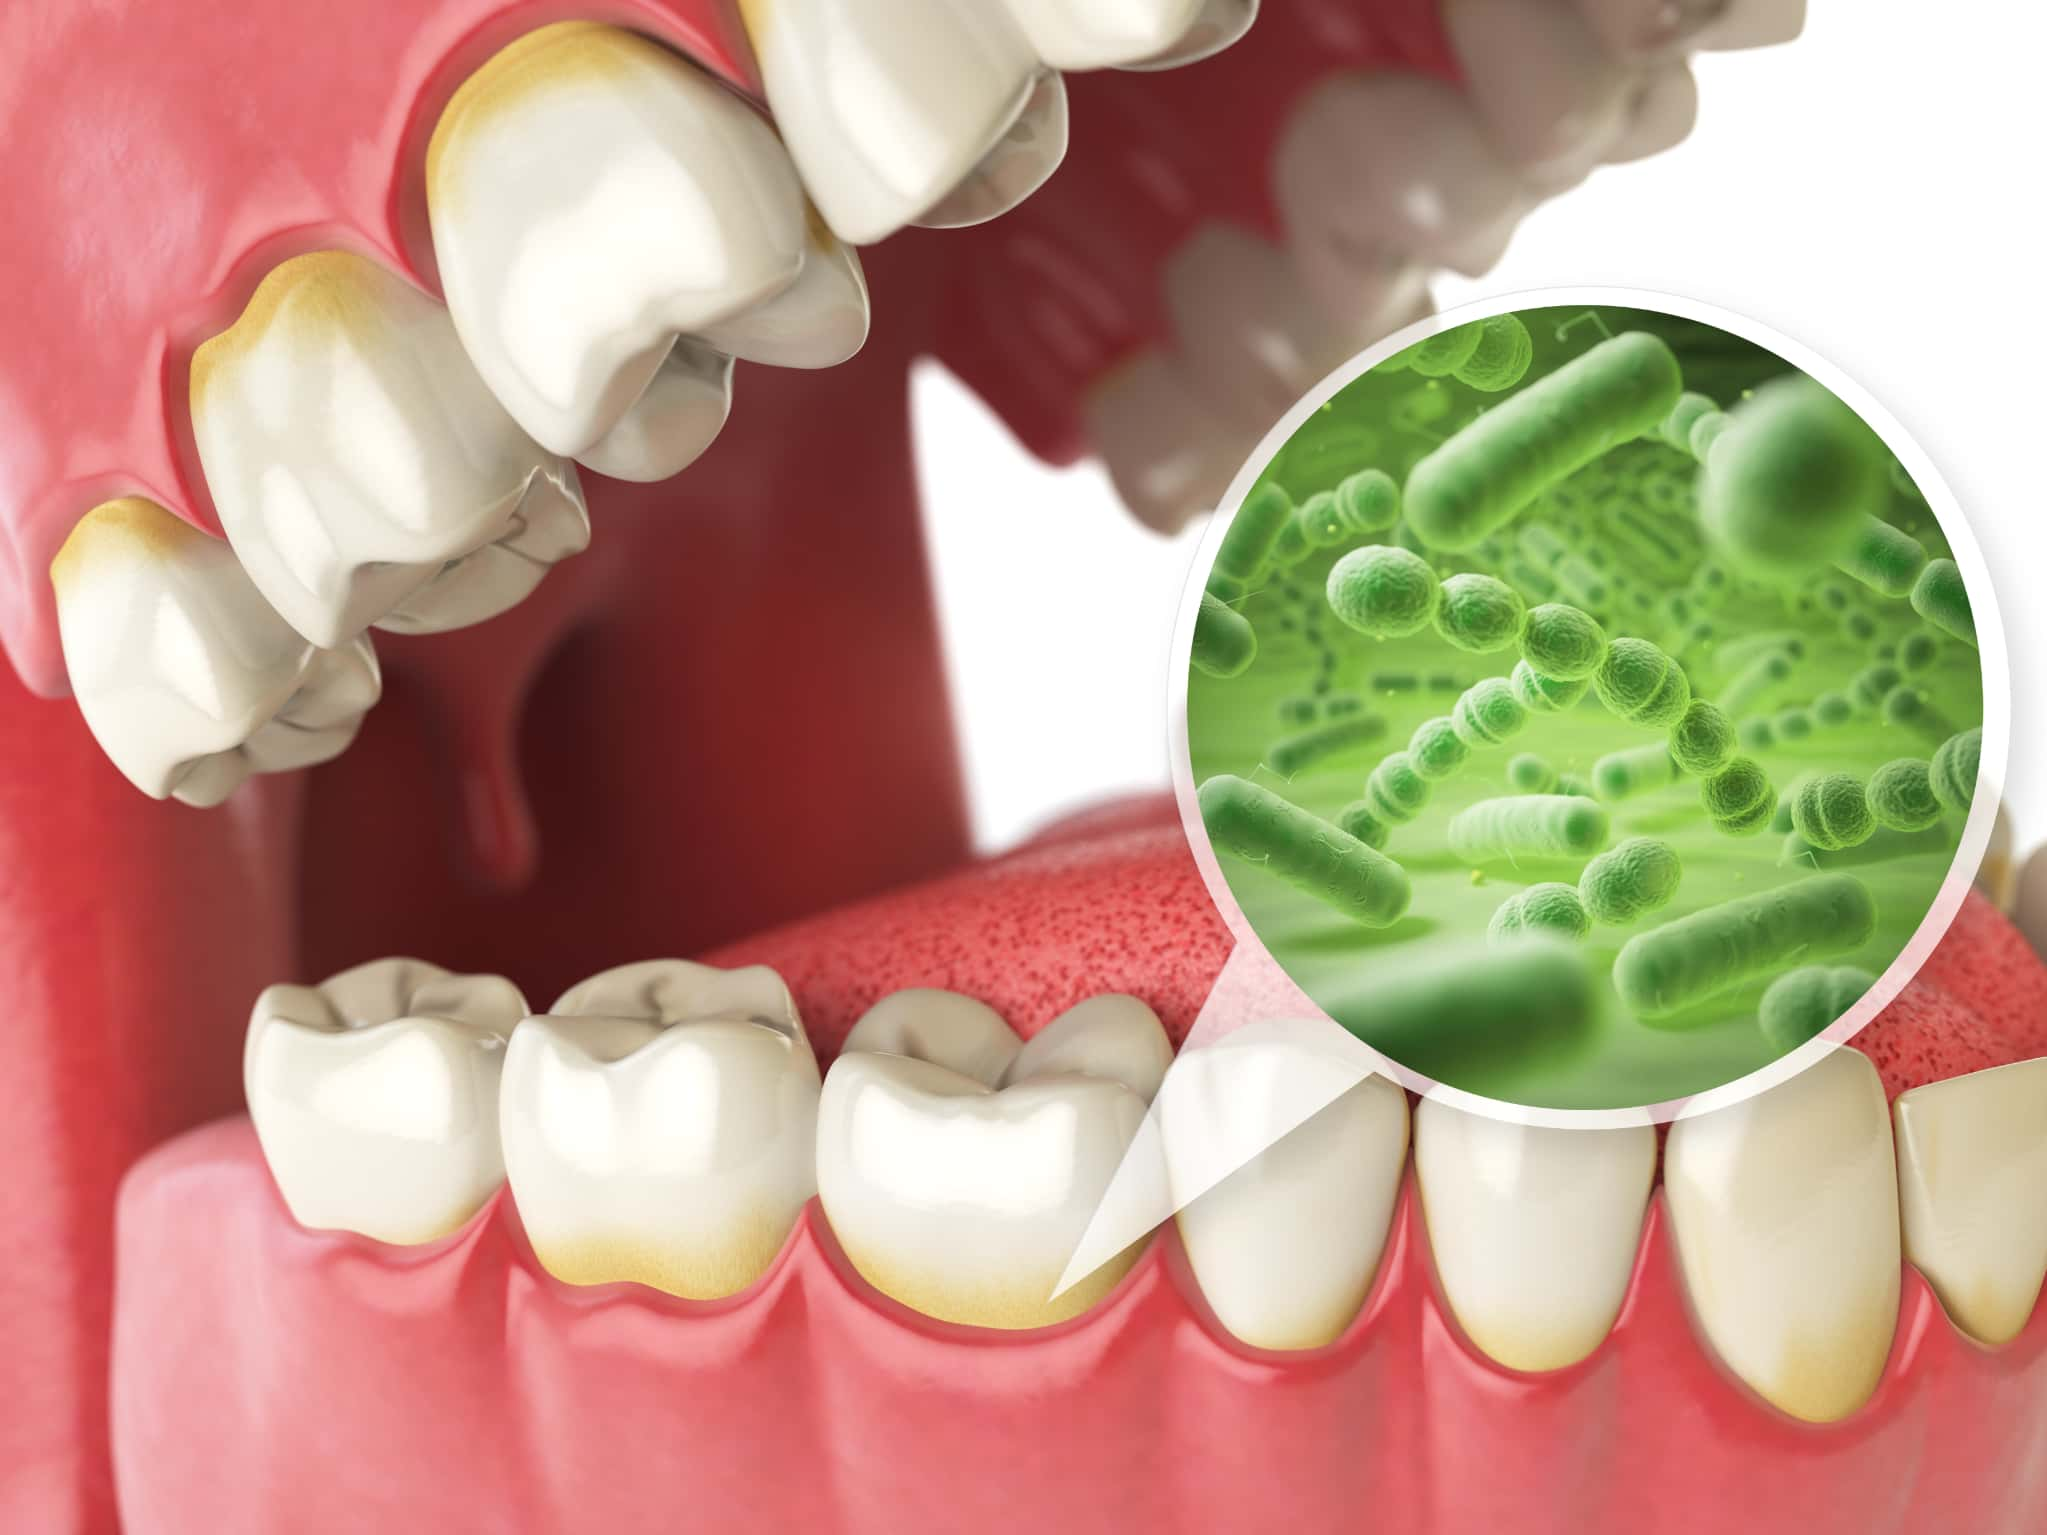

歯周病とは、歯と歯ぐきの間に細菌が入り込み、炎症を起こすことで歯ぐきが赤く腫れたり、出血したりする病気です。放置すると、炎症が歯を支える歯槽骨にまで広がっていきます。その結果、歯がぐらつき、最終的には抜け落ちることもある病気です。

歯周病の初期段階が、歯肉炎です。歯と歯茎の間にプラーク(歯垢)が蓄積して細菌が繁殖し、歯茎に炎症が起こります。歯茎が赤く腫れたり、ブラッシング時に軽い出血が見られることがありますが、痛みは少なく気づきにくい段階です。